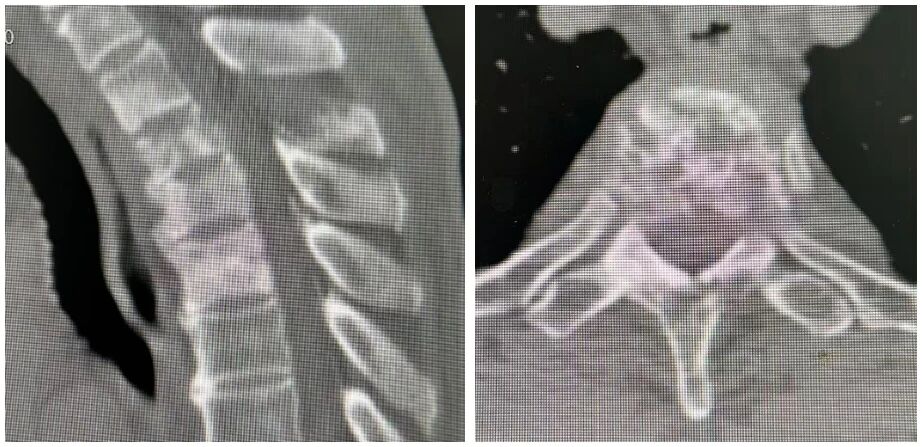

近期,他因双下肢麻木、乏力再次入益阳市中心医院治疗。完善相关检查后诊断为脊柱转移瘤、双下肢不全瘫(Frankle分级 C级),肿瘤细胞转移至上胸椎,胸3-4层面脊髓受压,导致患者双下肢肌力评级仅为1-2级,乳头以下平面感觉丢失。

(磁共振显示胸椎椎体骨质破坏)

由于患者高龄,基础情况差,且手术部位为颈胸交界处,手术难度大,风险高,稍有不慎就可能损伤神经导致瘫痪,甚至引发大出血危及生命。术前,医院组织全院会诊,召集脊柱外科、肿瘤内科、麻醉科、影像科、康复医学科等专家讨论手术方案及术后康复问题。

专家团队经过反复论证,最终决定为彭爹行颈7-胸5椎弓根螺钉内固定+胸3、4病灶切除+钛笼置入术。